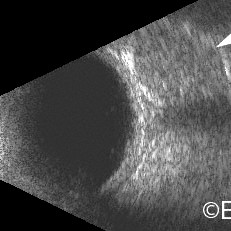

Choroidal osteoma

Choroidal osteoma and its associated orbital shadowing (arrow).